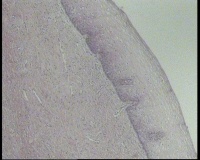

镜下见鳞状上皮大部分如(图1) ,仅局灶鳞状上皮异型(图2-4),细胞似牵拉变形,部分腺腔内见异型细胞团,这些细胞跟LEEP刀手术电凝有关系吗?这个怎么报?累腺明显,上皮图1怎么报?能报CINII—III累及腺体吗?还是宫颈高级别鳞状上皮内病变累及腺体

图1